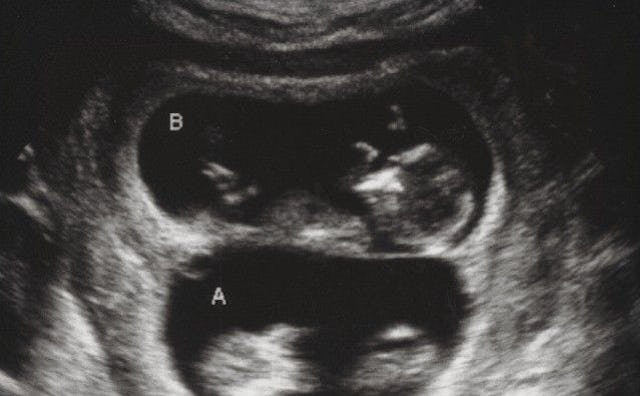

“Okay” says the sonogram technician as she moves the wand to the other side of my belly. “And what do you see now?”

“Um, the baby turned over?” I guess, since the right-facing profile was now a left-facing profile.

“Nooooo.”

“Two babies.”

“Well, let’s see…” as she gently pushes me back to the 3/4 laying down position, and she proceeds to point out all number of things that should explain the situation to me – two umbilical cords, two placentas, two amniotic sacks, and then there, clear as day – four arms, four legs, and two heads.